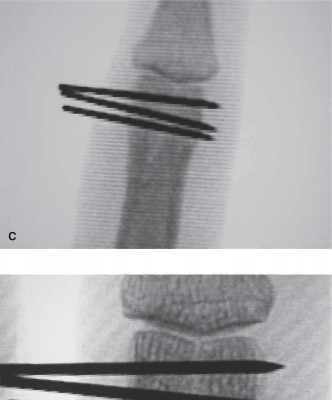

The correct answer is (E). This is an unstable injury as evidenced by the patient’s description of the deformity at the time of injury and by the radiographs seen in the office. The fracture is displaced and is an intra-articular fracture. There is an articular stepoff. Furthermore, it is an oblique fracture. All of these features indicate that this is an unstable injury, and treatment by closed means is unlikely to be successful. In fractures that are completely nondisplaced, closed nonoperative

treatment remains an option. However, in this instance where there is articular stepoff and displacement has occurred, it is vital to restore the length of the fragment, and more critically restore articular congruity especially in this young person. Closed reduction and percutaneous fixation as shown in the postoperative radiographs can be effective if perfect reduction of the joint is achieved (Fig. 4–10C to E). Failure to achieve perfect joint reduction by closed means necessitates an open reduction and treatment with either pins or screws.

Figure 4–10 C–E